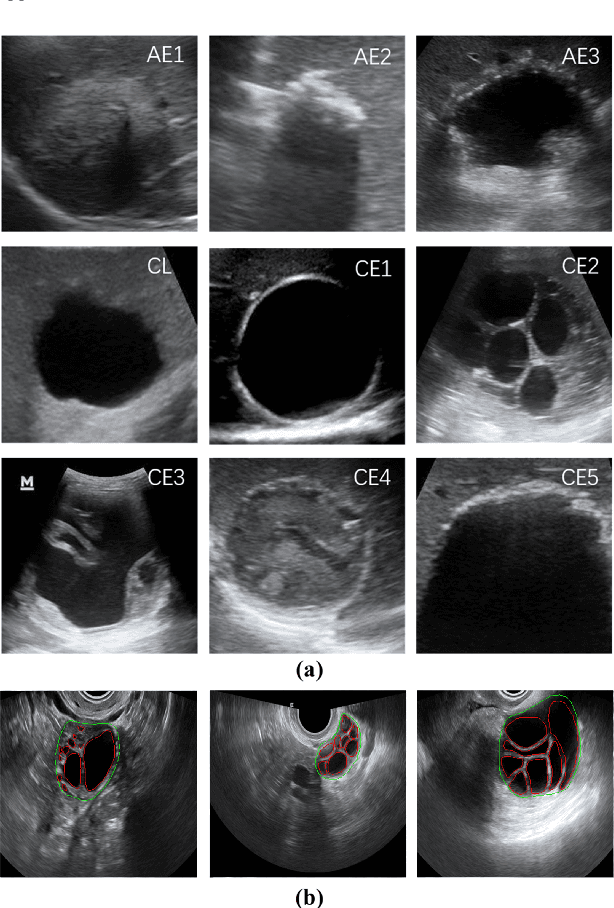

Abstract:Different from handcrafted features, deep neural networks can automatically learn task-specific features from data. Due to this data-driven nature, they have achieved remarkable success in various areas. However, manual design and selection of suitable network architectures are time-consuming and require substantial effort of human experts. To address this problem, researchers have proposed neural architecture search (NAS) algorithms which can automatically generate network architectures but suffer from heavy computational cost and instability if searching from scratch. In this paper, we propose a hybrid NAS framework for ultrasound (US) image classification and segmentation. The hybrid framework consists of a pre-trained backbone and several searched cells (i.e., network building blocks), which takes advantage of the strengths of both NAS and the expert knowledge from existing convolutional neural networks. Specifically, two effective and lightweight operations, a mixed depth-wise convolution operator and a squeeze-and-excitation block, are introduced into the candidate operations to enhance the variety and capacity of the searched cells. These two operations not only decrease model parameters but also boost network performance. Moreover, we propose a re-aggregation strategy for the searched cells, aiming to further improve the performance for different vision tasks. We tested our method on two large US image datasets, including a 9-class echinococcosis dataset containing 9566 images for classification and an ovary dataset containing 3204 images for segmentation. Ablation experiments and comparison with other handcrafted or automatically searched architectures demonstrate that our method can generate more powerful and lightweight models for the above US image classification and segmentation tasks.